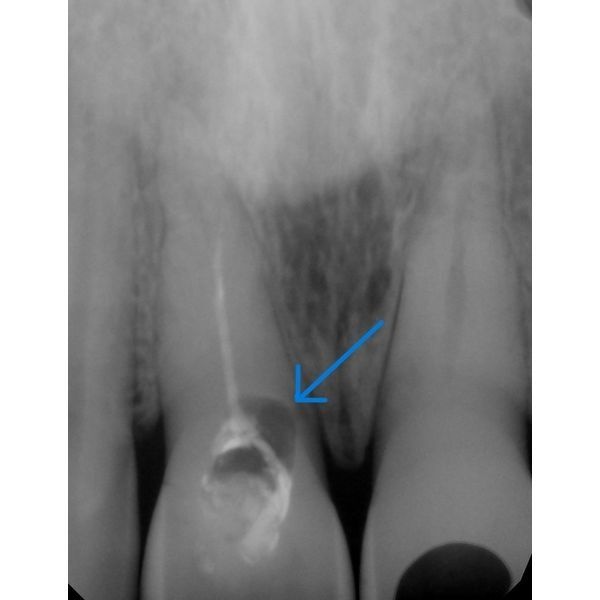

На компьютерной томографии (КТ) наблюдался рецидивный кариес. Определялся плохо запломбированный корневой канал. Ширина кости — 7 мм, высота — 14 мм, плотность — 3-й класс (относительно нормальная костная ткань).

Патологический перелом зуба 1.1.